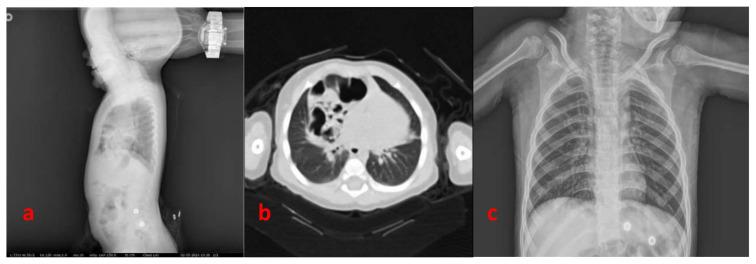

双端口腹腔镜辅助体外缝合技术与开放手术修补 Morgagni 疝的比较。

Comparison of double-port laparoscopic-assisted extracorporeal suture technique and open surgical repair for Morgagni hernia.